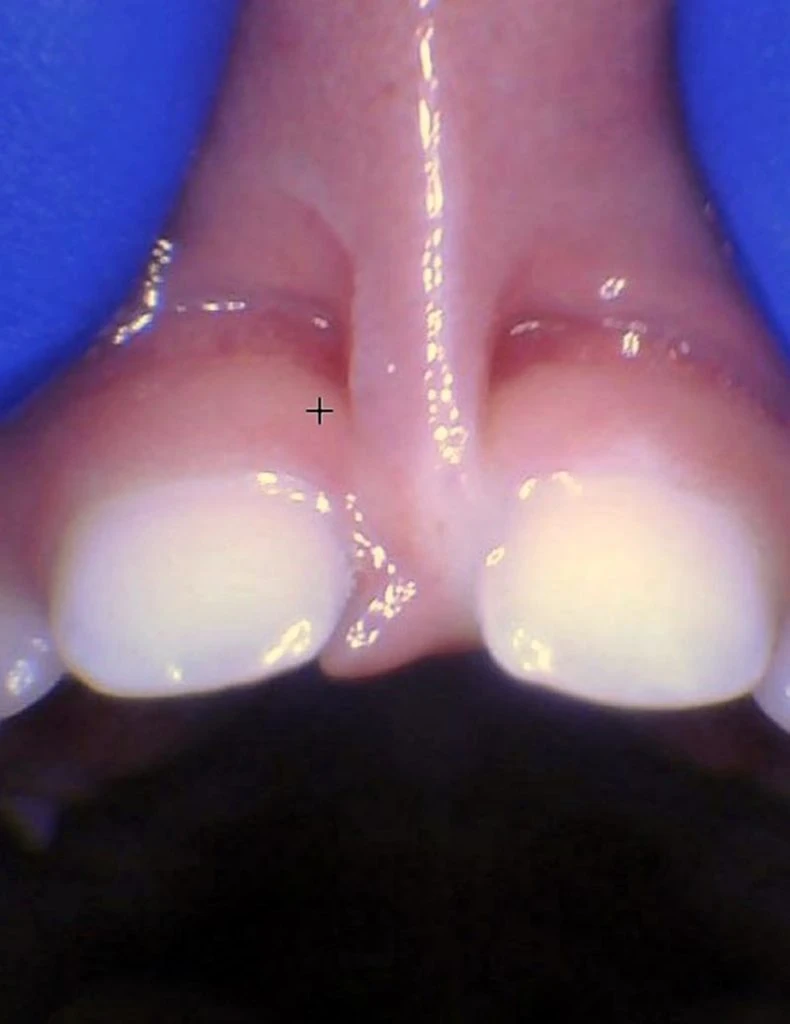

These images show the spectrum of lip restriction in an infant.

View lip restrictions

These images show the spectrum of lip restriction in a child.